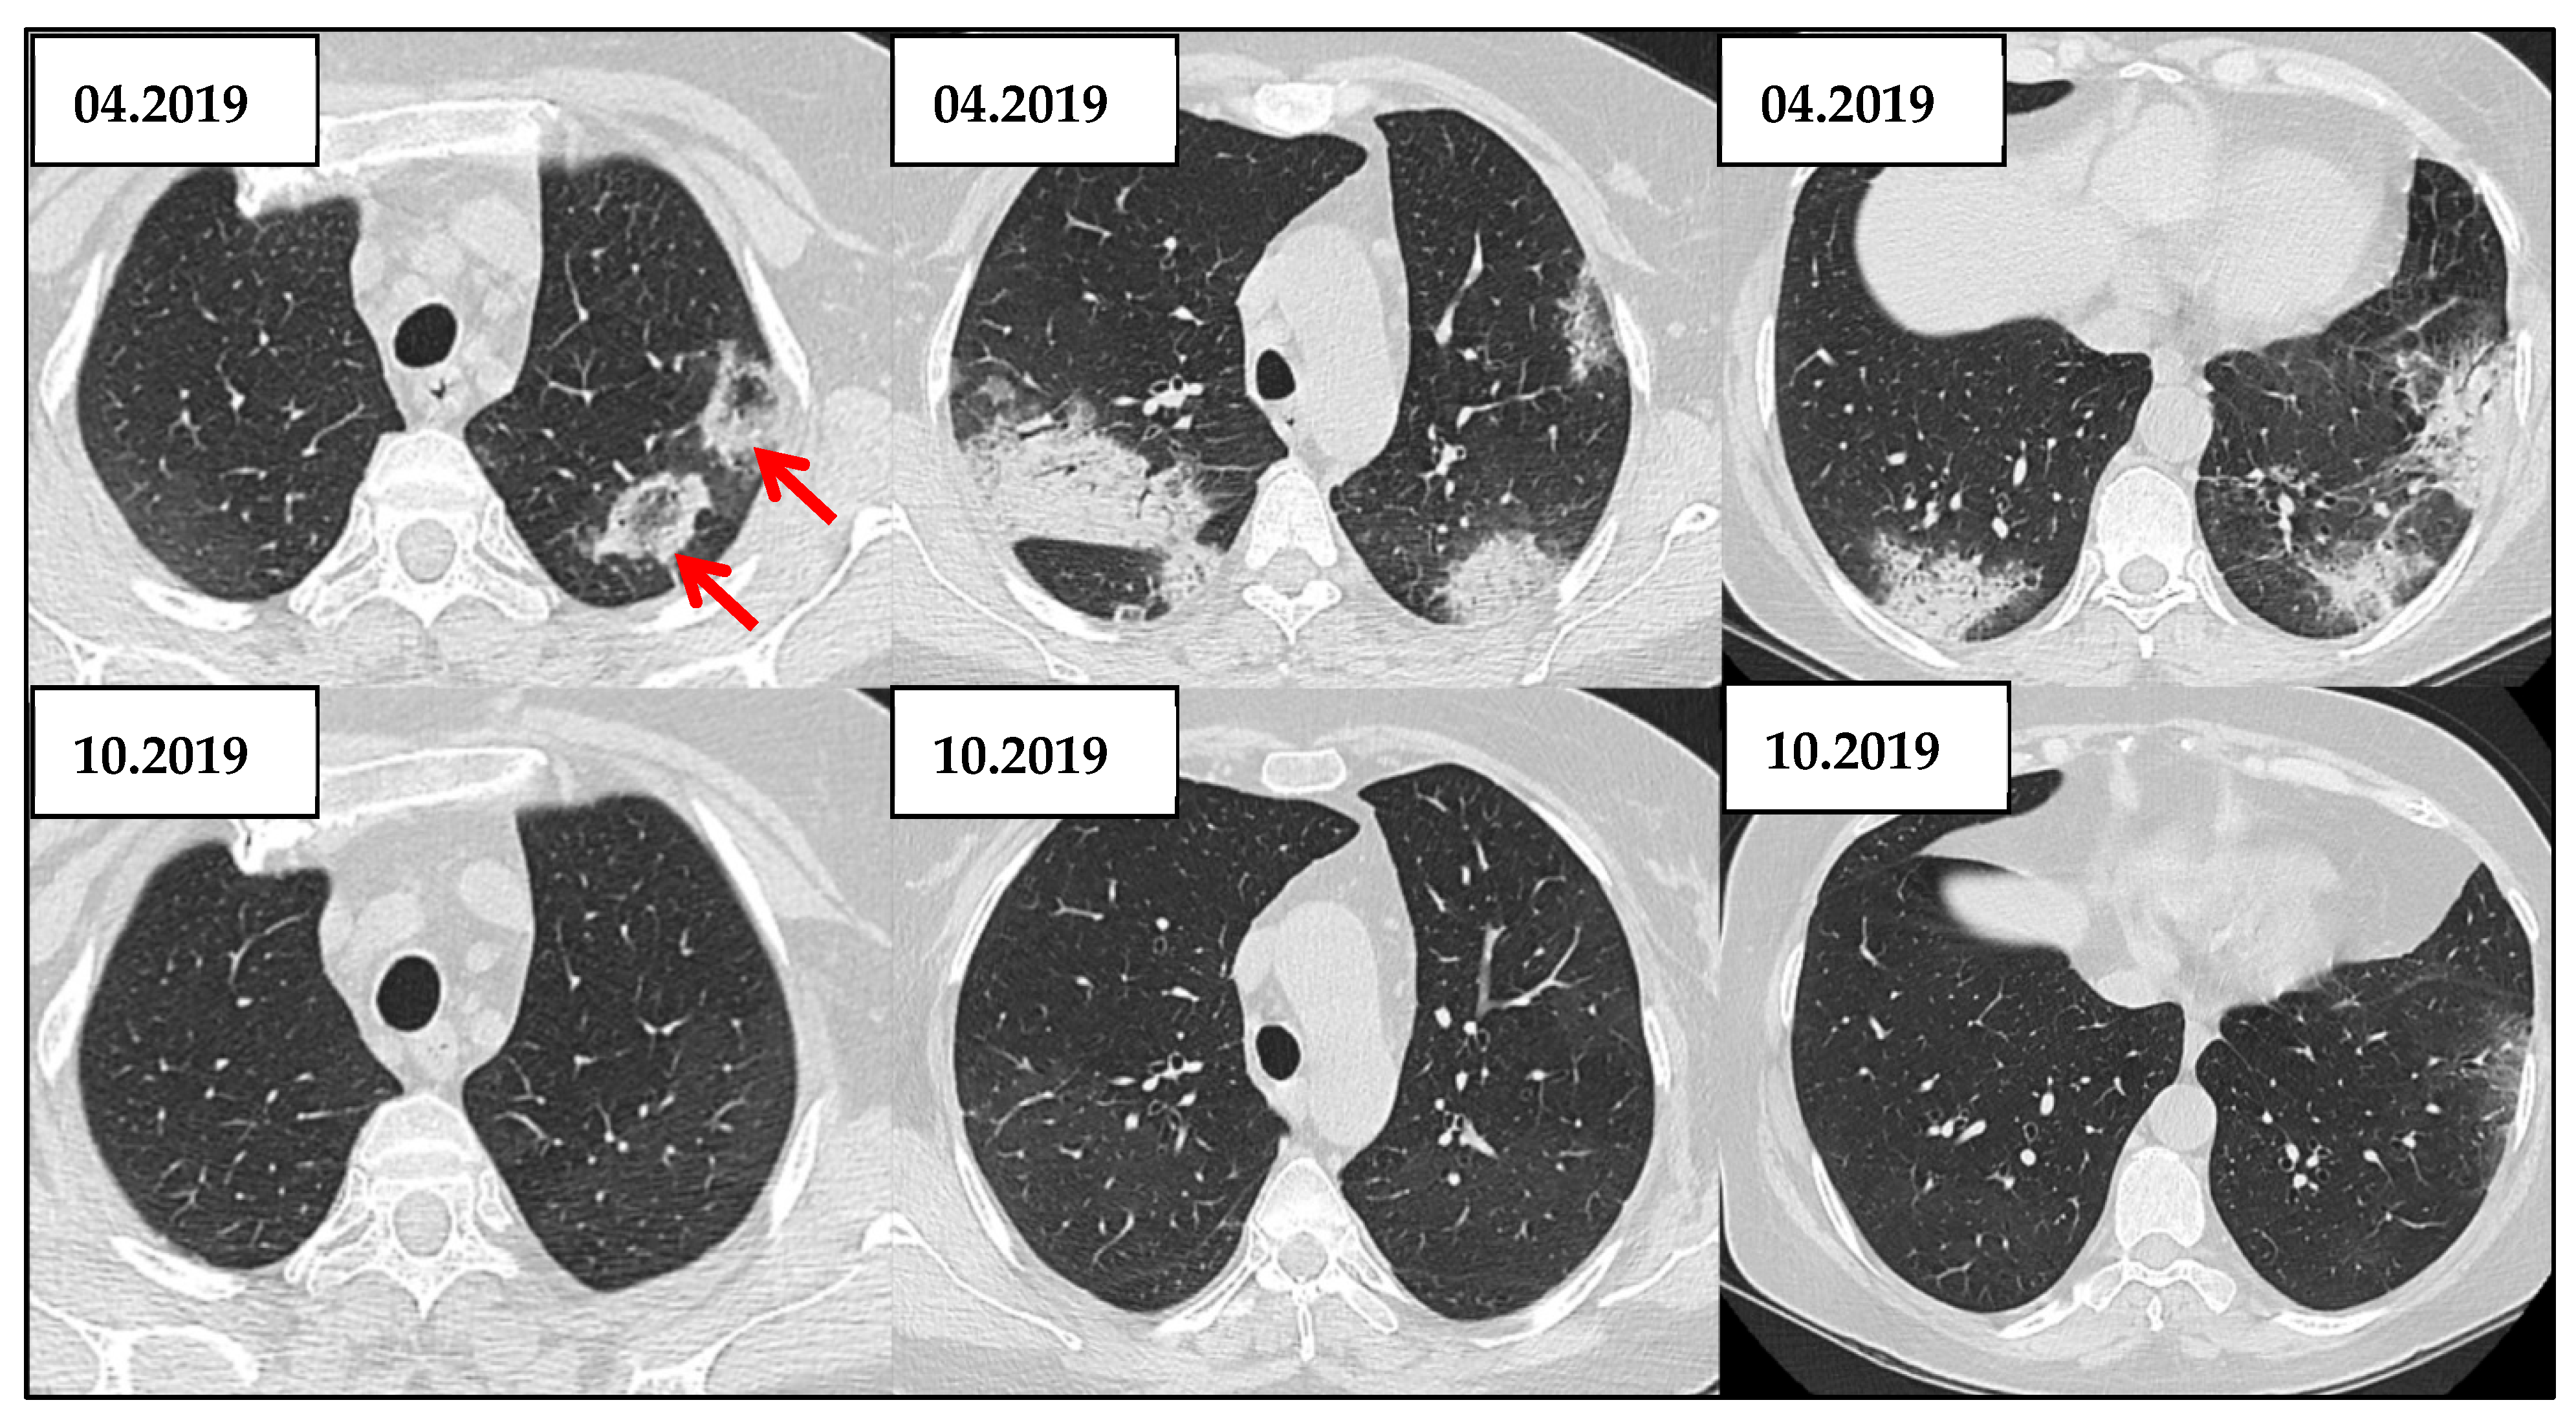

3.3.3. OP Pattern

| HRCT Patterns | - UIP is the most common pattern (~40–60%)—strong negative prognostic marker - NSIP (~15–25%) - OP and mixed types less frequent. (<20%)  | [43] |